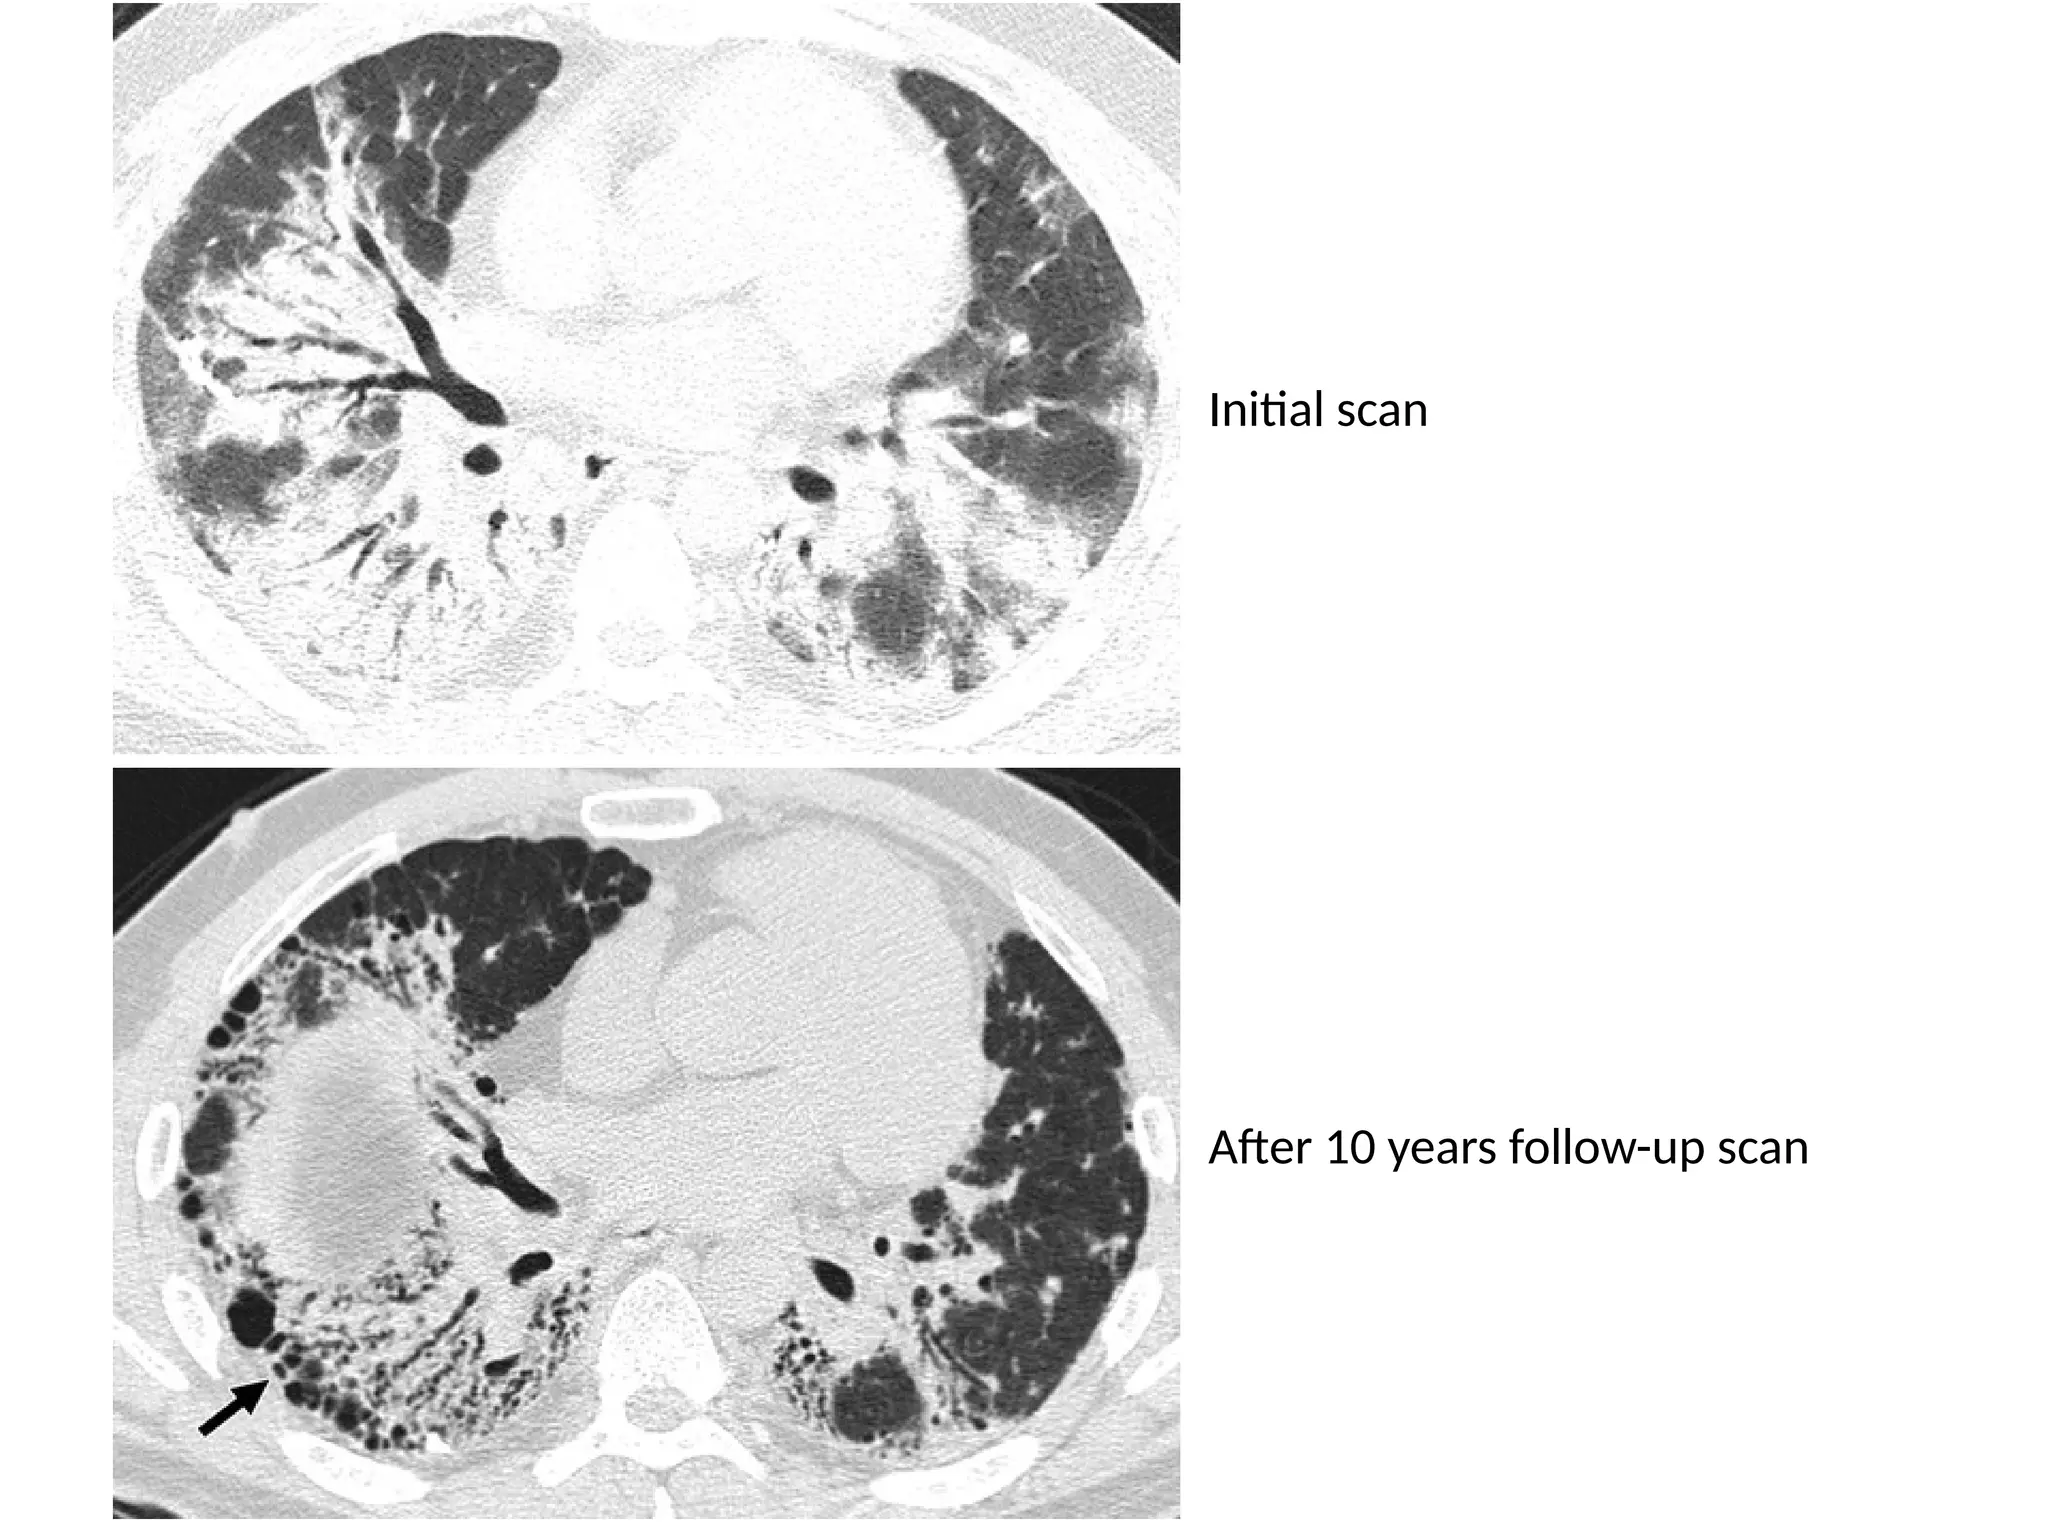

Initial scan

After 10 years follow-up scan

• Organising pneumonia •Organizing pneumonia represents an inflammatory process in which the healing process is characterized by organization and cicatrization of the exudate rather than by resolution and resorption. It is also described as 'unresolved pneumonia’. • Patients with COP typically present with a several-month history of nonproductive cough. • Many cases are idiopathic, but OP may also be seen in patients with pulmonary infection, drug reactions, collagen vascular disease, Wegener's granulomatosis and after toxic- fume inhalation.

Initial scan After 10years follow-up scan